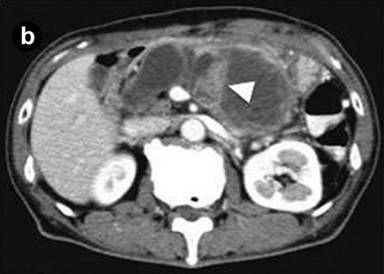

A 75-year-old man was admitted to the hospital because of acute onset of severe epigastric pain and body weight loss. On physical examination, palpable mass and tenderness of upper abdomen was noted. Laboratory studies revealed elevated C-reactive protein (7.0 mg/dL; reference range: 0-0.5 mg/dL), CEA (39.7 ng/mL; reference range: 0-5 ng/mL), CA 19-9 (62.3 U/mL; reference range: 0-37 U/mL) and HbA1c (13.2%; reference range: 3.4-5.8%). Results of complete blood count, plasma levels of electrolytes, tests of coagulation, amylase, lipase, kidney and liver function were within normal limits. Computed tomography (CT) and magnetic resonance imaging (MRI) of the abdomen showed a markedly dilated main pancreatic duct (45 mm), a papillary tumor (20 mm in diameter) protruding into the main pancreatic duct of the distal pancreas and splenic vein obstruction (Figure 1abc). On duodenoscopy with a lateral viewing of endoscope, mucus was discharged from the enlarged papilla of Vater (Figure 2a). Peroral pancreatoscopy was performed, revealing the papillary tumor on the main pancreatic duct (Figure 2b). Pathological examination of biopsy specimens of the tumor showed papillary mucinous adenoma (Figure 2c).

Figure1. a. Computed tomography (CT) showed a markedly dilated main pancreatic duct (45 mm, arrow) and splenic vein obstruction (arrowhead). b. CT showed a papillary tumor (20 mm in diameter) protruding into the main pancreatic duct of the distal pancreas (arrowhead). c. Magnetic resonance cholangiopancreatography (MRCP) showed a markedly dilated main pancreatic duct. |